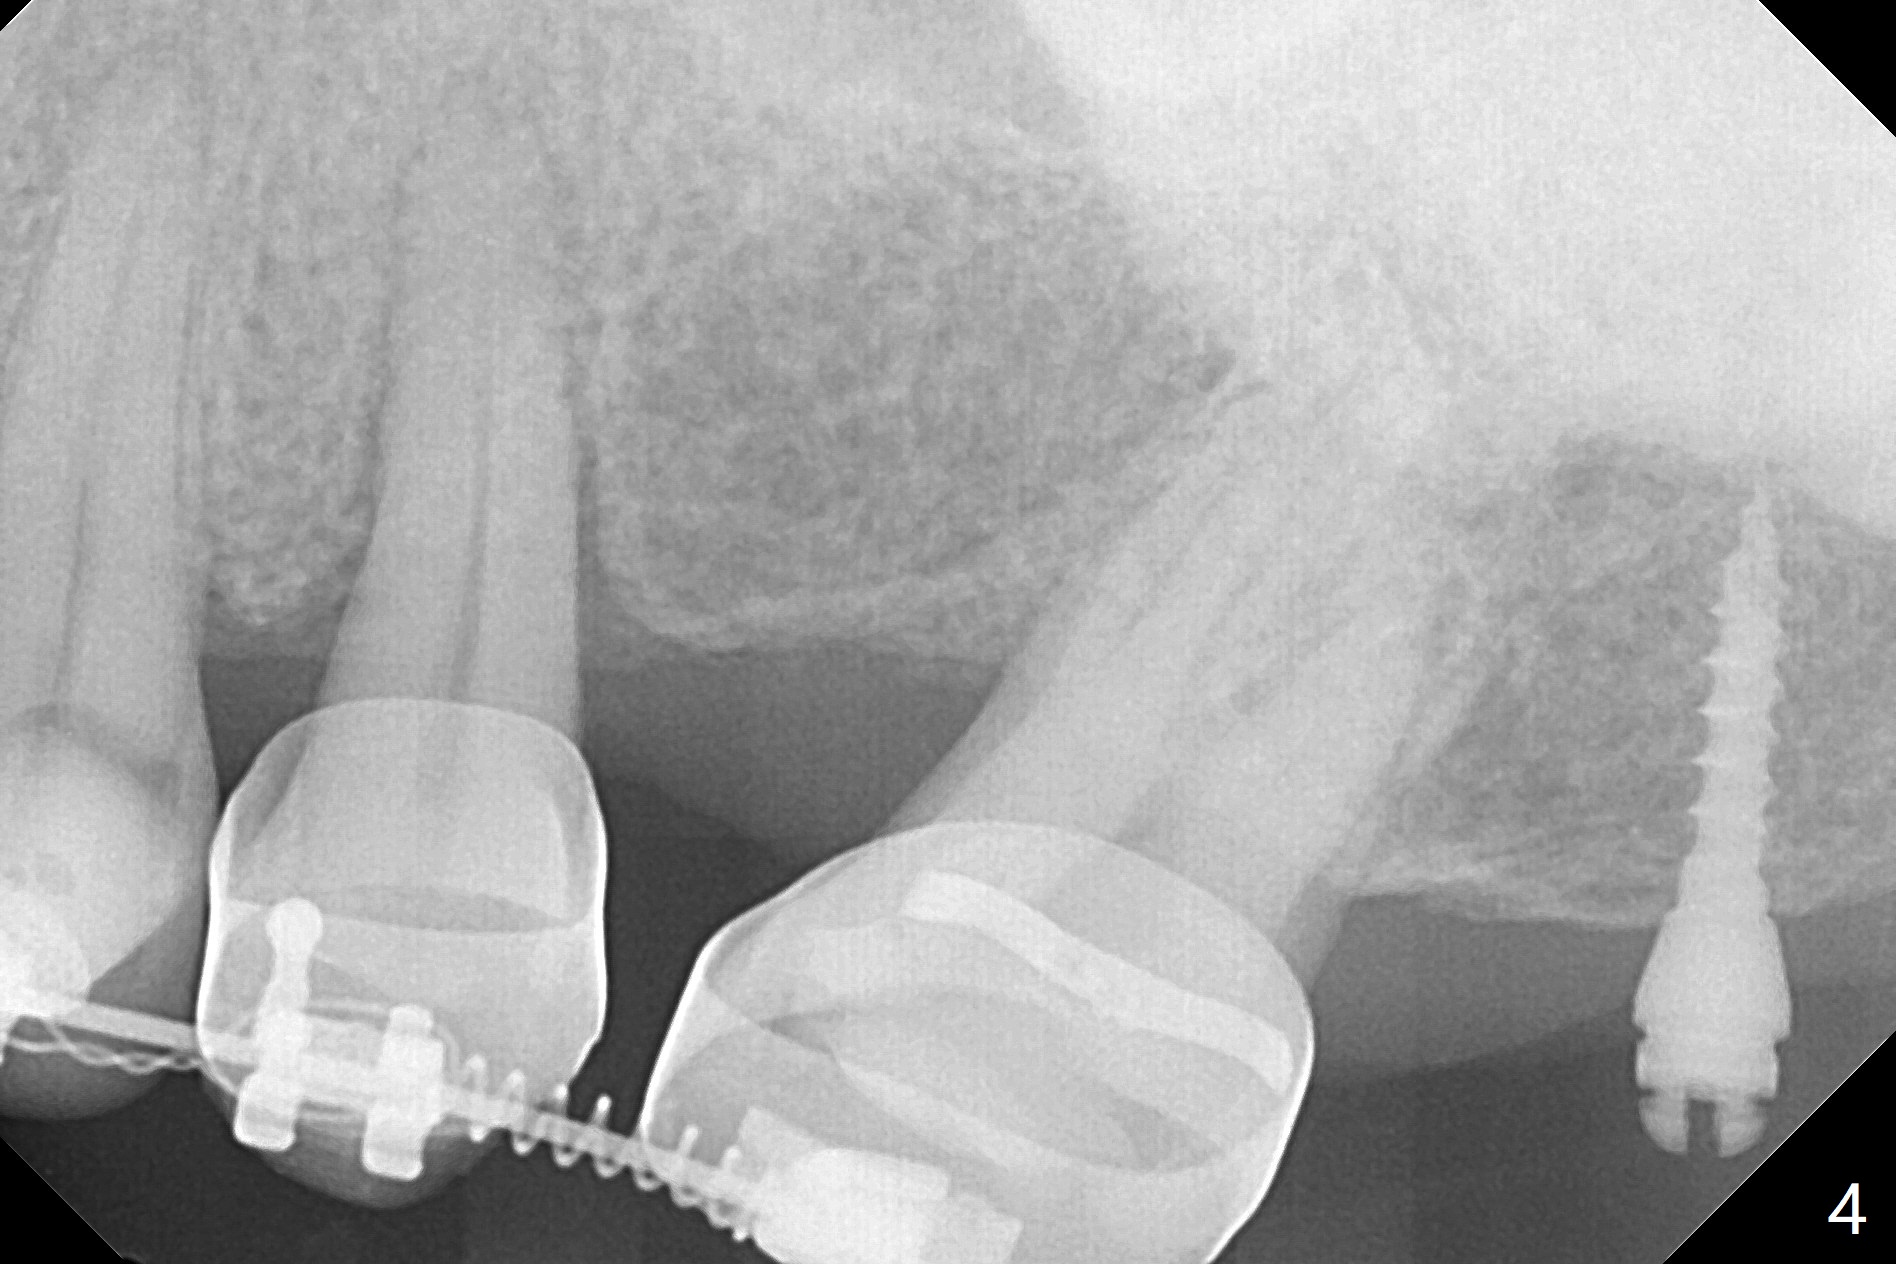

为了在左上6,左下7种植,使用右上3至左上5作为支抗推左上7远中,但是六个月效果不显著(图一),CT显示阻生牙(图一,二:8)没有阻挡。7远中植入1.6x8毫米微型植体,不过接近7根尖(图三),微型植体应该改变角度,而且往远中颊侧移位。最后效果不错(图四),植体马上启用(图五),而且同时取模做左下7导板。在微型植体牵引下,左上7的确往远中移位(图六,与图四对比),但是植体松动,马上植入3x10(2)毫米一段式植体,由于8阻挡,后者没有完全就位,稳定性差,没有启动。几天后也脱落。病人急着完成治疗,因为咀嚼困难。补救方法便是拔除阻生牙9(图七:x),让植体完全就位。切开后发现牙槽嵴处严重骨质吸收缺损(图八:D),离7很近,不适合种植。拔除8后(图九:S(socket)),两处植骨(粘性,图十),覆盖PRF膜,缝合。矫正九个月6空间相当双尖牙(图十二),还想增加2毫米才种植,病人急于完成治疗,所以再次植入微型植体,不同之处是切开,发现7远中颊侧骨质密度低(用探针),因此微型植体在腭侧植入(图十一:P),扭力似乎高,1.6x8毫米植体仿佛植入8牙槽窝(图十二:红虚线)。微型植体牵引一个月,磨牙缺牙间隙大约前磨牙大小,准备在远中(图十三)植入直径小植体(图十四),当后者整合时,用它继续推7。